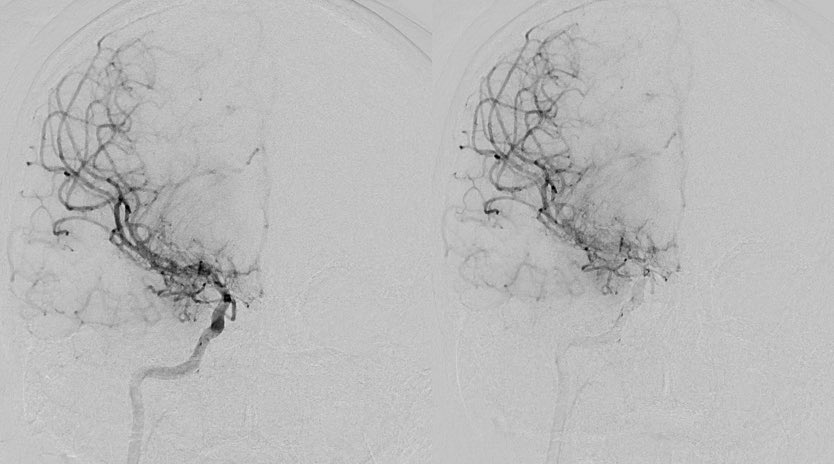

Imaging of Moyamoya disease/syndrome Imaging: Thread-like intracranial ICA/MCA with attenuated branches and “puff of smoke” appearance on DSA Co